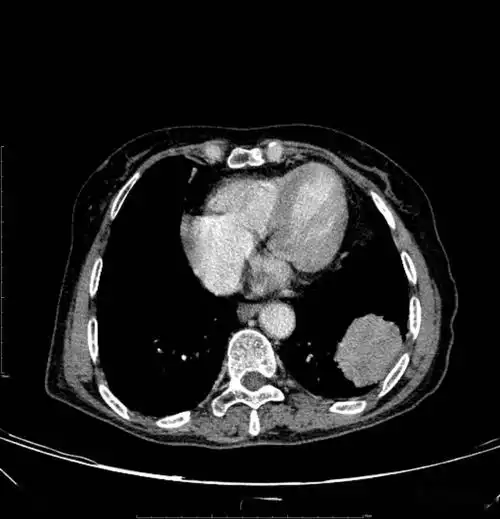

胸部ct平扫示左下肺占位肺癌